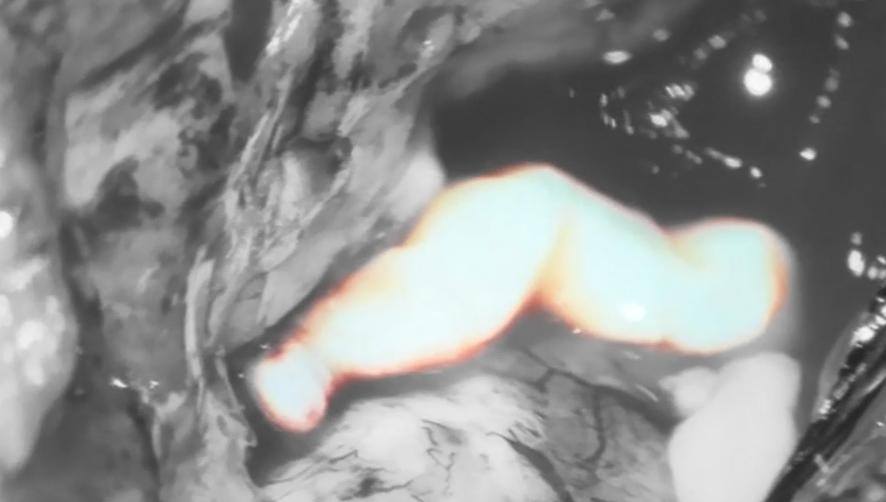

神经外十科团队使用电磁导航定位,在高清显微镜放大下手术。“看到一条面条状的活虫在蠕动。”手术医生小心翼翼地将寄生虫活捉,并很好地保护脑神经组织。

术中可见裂头蚴在蠕动